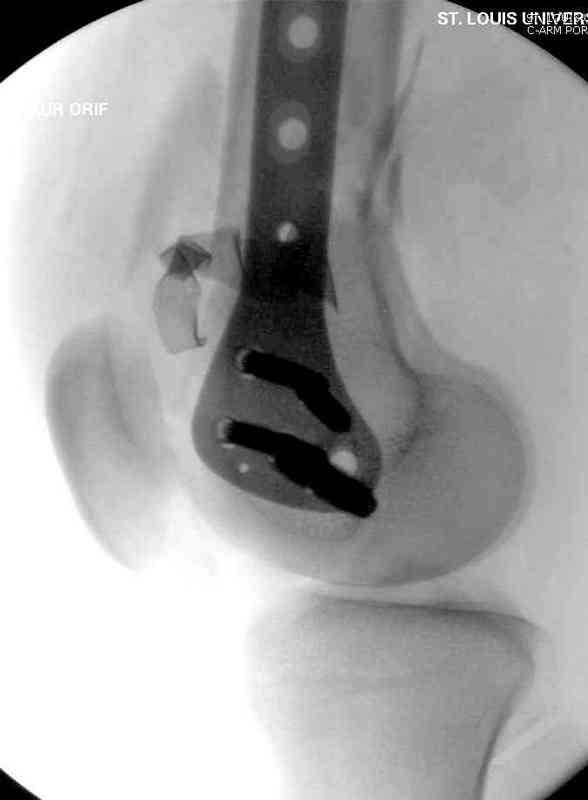

Доступ был латеральный, при вскрытии с задней

поверхности бедра обнаружили кровотечение. Поднятием давления на заранее установленном турникете на конечности проконтролировали кровотечение.

В данном случае мы не ставили осуществление гемостаза приоритетным, после 30 минут больной оставлен вызванному сосудистому хирургу со стабильной фиксацией бедра. Несмотря на выбранный передне-медиальный доступ, хирург произвел восстановление сосудистого повреждения.

Латерально пластину защитили ушиванием

илио-тибиального тракта, а медиальная сторона была ушита мышцей, и все раны закрыли ваккумированием (VAC)

На третий день после Irrigation & Debridment закрыли все раны за исключением компартментальной раны из-за отека, медиально в дефект кости установили Putty Grafton Bone Substitute. На компартментальную рану вакуум и мероприятия по сближению краев раны резиновой стяжкой.

На 9й день с момента травмы ушили рану без натяжения. Больной получает реабилитацию, движения коленного сустава с помощи CPM-continuous passive motion machine. Сегодня выписан.